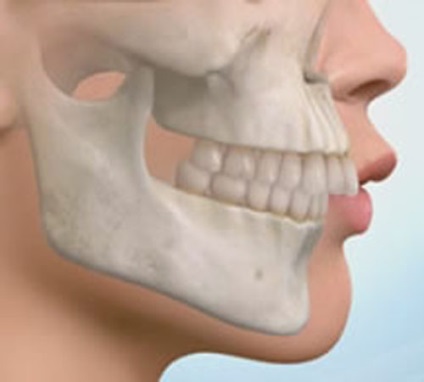

De ce malocluzie pare să-ți o problemă minoră?

Da, aceasta nu împiedică să trăiască, să mănânce, de somn, de studiu și de lucru. În cazul în care dinții nu sunt la întâmplare, iar aspectul nu este prea suferă. Dar toate aceeași în adâncul interiorul nostru brutalizează este o întrebare legitimă: ce amenință malocluzie. în cazul în care acest lucru nu ia medicația?

consecințele periculoase ale malocluzii

Astfel, consecințele malocluzii sunt periculoase și nu foarte mult. Iar apariția celui de al doilea grup. Sunt serios: asimetrie facială, o curbură în față a maxilarului sau dinții - doar vârful iceberg-ului, rezultatul cel mai inofensiv al lipsei de tratament competent și în timp util, ortodont. Da, poate fi urât și neplăcut (mai ales in adolescenta si la maturitate), dar nu mai mult.

consecințe periculoase sunt mult mai profunde, iar persoana ignorant ele sunt greu de ghicit tu însuți.

mușcătură corect așa-numitele pentru un motiv. Lui „truc“ este faptul că fălcile sunt închise în poziția corectă, care ajută la distribuirea uniformă a sarcinii în timpul mestecării, adică, în timpul mesei. Gnaws Ești nuci sau bomboane, lăcrimarea bucăți de friptură sau să mănânce alimente moi, dinții lucrează în același mod și ritmul. În cazul în care rândurile de oblici sau mutat într-o parte sau alta, muncitorii sunt doar niște dinți, în timp ce altele se odihnesc.

2. Poziția incorectă a fălcilor și a lucrărilor

Observați cum rândul său bruscă a capului sau trunchi poate fi auzit clic sau există durere în nervul? Falca este strâns legat de lobul temporal, inclusiv terminațiile nervoase. Din activitatea fălcilor în poziție greșită poate provoca dureri de cap, oboseală, dureri de spate, făcând clic în locuri neașteptate, și chiar și doar disconfort în timpul mânca.